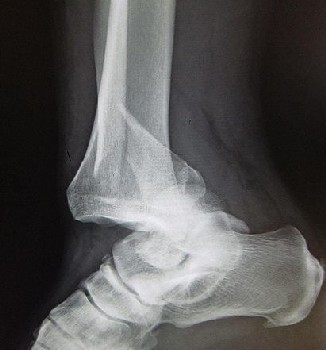

Sea surgeon John Atkins provides the most extensive explanation of reducing a dislocated ankle.

Image: James Hielman - Forward Dislocation of the Ankle

Extension should be made with one Hand on the Metacarpus [probably meaning the metatarsels], the other on the Heel, while an Assistant holds the Leg the same Time: Having collected from the aforegoing Signs, how the Head of the Astragalus [Talus] lies distorted, wring the Foot the contrary Way; or when the Recession is small, or but suspected, press gently with your Fingers about the Joint, (when at its Extension,) to restore the Deformity.5

Wiseman adds a last thought on reducing a dislocated ankle. "In case the Extension by your Hands suffice not, you may make use of Pulleys or other Engines."6 He doesn't give any further details, although Woodall's beloved commander comes to mind.